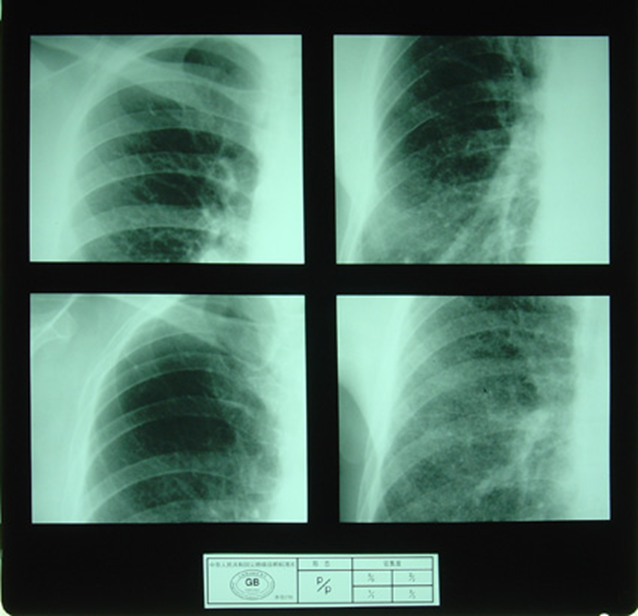

(2)X射线胸片表现:矽肺X射线胸片影像是肺组织矽肺病理形态在X射线胸片的反映,是“形”和“影”的关系,与肺内粉尘蓄积、肺组织纤维化的病变程度有一定相关关系,但由于多种原因的影响,并非完全一致。这种X射线胸片改变表现为X射线通过病变组织和正常组织对X射线吸收率的变化,呈现发“白”的圆形或不规则形小阴影,作为矽肺诊断依据。X射线胸片上其他影像,如肺门变化、肺气肿、肺纹理和胸膜变化,对矽肺诊断也有参考价值。在X射线胸片上,肺野内直径或宽度不超过10mm的阴影。小阴影按其形成分为圆形和不规则形两类。

1)圆形小阴影:是矽肺最常见和最重要的一种X线表现形态,其病理基础以结节型矽肺为主,呈圆或近似圆形,边缘整齐或不整齐,直径小于10mm,按直径大小分为p(<1.5mm)、q(1.5~3.0mm)、r(3.0~10mm)三种类型。p类小阴影主要是不太成熟的矽结节或非结节性纤维化灶的影像,q、r类小阴影主要是成熟和较成熟的矽结节,或为若干个小矽结节的影像重叠。圆形小阴影早期多分布在两肺中下区,随病变进展,数量增多,直径增大,密集度增加,波及两上肺区。

圆形小阴影(p类小阴影)

圆形小阴影(q类小阴影)

圆形小阴影(r类小阴影)

3)大阴影:在X射线胸片上,肺野内直径或宽度超过10mm的阴影,为晚期矽肺的重要X射线表现,形状有长条形、圆形、椭圆形、或不规则形,病理基础是团块状纤维化。大阴影的发展可由圆形小阴影增多、聚集,或不规则小阴影增粗、靠拢、重叠形成;多在两肺上区出现,逐渐融合成边缘较清楚、密度均匀一致的大阴影,常对称,形态多样,呈八字形等,也有先在一侧出现;大阴影周围一般有肺气肿带的X射线表现。

大阴影

尘肺壹期:有下列表现之一者:

a)有总体密集度1级的小阴影,分布范围至少达到2个肺区。

2)尘肺贰期:有下列表现之一者:

a) 有总体密集度2级的小阴影,分布范围超过4个肺区;

b)有总体密集度3级的小阴影,分布范围达到4个肺区。

3)尘肺叁期:有下列表现之一者:

a) 有大阴影出现,其长径不小于20mm,短径不小于10mm;

b)有总体密集度为3级的小阴影,分布范围超过4个肺区并有小阴影聚集;

c) 有总体密集度为3级的小阴影,分布范围超过4个肺区并有大阴影。

尘肺壹期

尘肺贰期

尘肺壹期

尘肺贰期

尘肺壹期

尘肺贰期

尘肺叁期